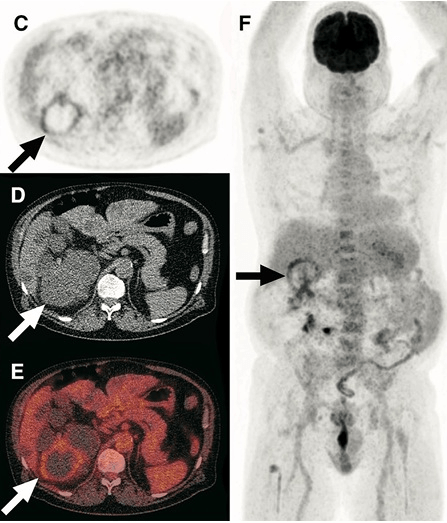

Infecção de Cistos na DRPAD — abordagem prática para diagnósticoInfecção de cistos na DRPAD continua sendo um desafio diagnóstico. O novo fluxograma KDIGO 2025 traz critérios clínicos e de imagem para orientar a investigação. Saiba quando considerar o PET/CT-FDG e como diferenciar infecção de hemorragia cística.